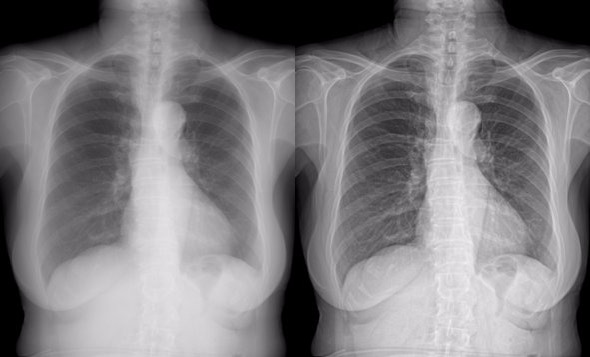

AcuImages' algorithms and software dramatically improve diagnostic confidence in almost all medical imaging modalities,

which includes but not limited to:

Original Enhanced